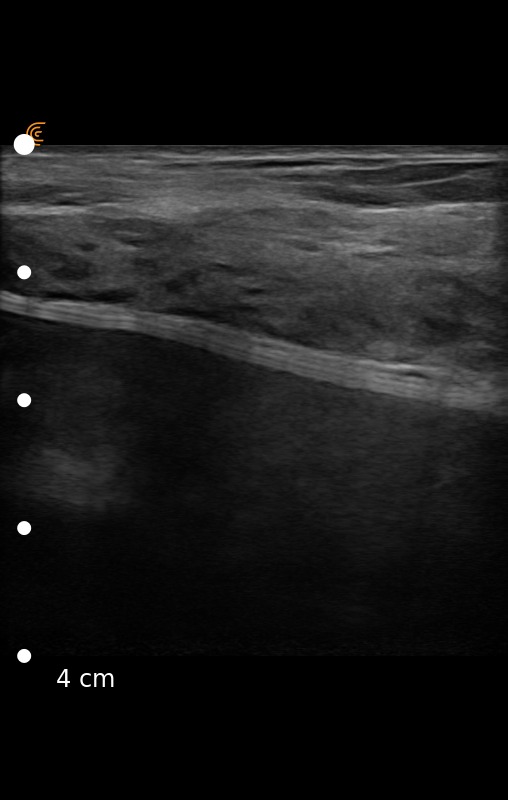

According to the FDA, ultrasound is an indispensable tool for plastic surgeons, for example, to regularly screen patients to detect silent ruptures.1 Dr. Roldan agrees. He recently shared ultrasound images captured on a patient with a ruptured silicon gel breast implant using the Clarius L7 HD Scanner. Can you identify the ruptured implant?

The right image clearly shows the stepladder sign, which are horizontally stacked echogenic lines traversing through the implant. Dr. Roldan confirmed the intracapsular rupture during the explantation surgery. The left ultrasound image includes a normal scan of the left breast.